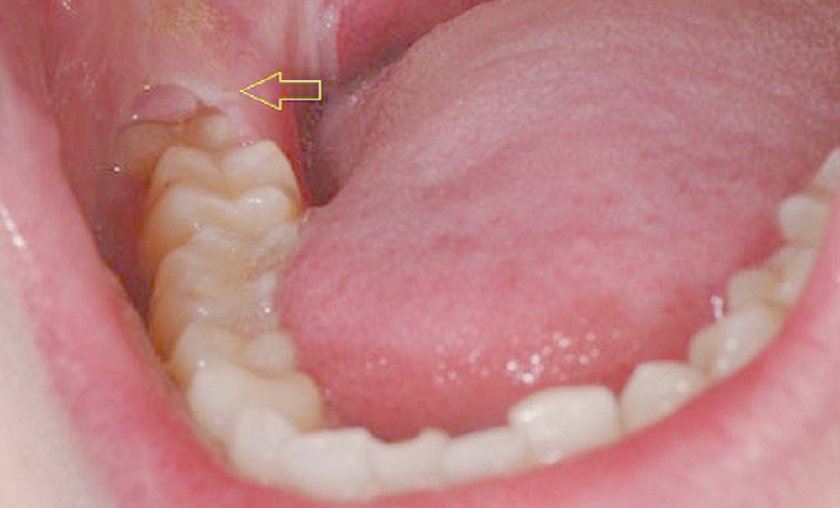

Do răng số 8 mọc muộn hơn các răng khác nên không còn nhiều khoảng trống cho răng số 8 mọc. Vì thế dễ dẫn đến tình trạng răng số 8 bị mọc lệch, mọc ngầm hoặc chỉ nhú một chút, dễ bị lợi trùm gây đau nhức khó chịu. Răng số 8 nằm ở vị trí sâu nhất trong khoang miệng nên khá khó trong việc làm sạch, nên răng rất dễ bị sâu hoặc gặp những vấn đề về nướu.

Răng số 8 mọc ở vị trí nào